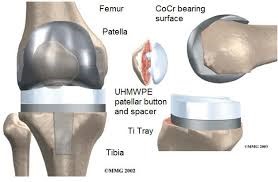

El que se usa de manera normal con excelentes resultados a largo plazo es la prótesis total de rodilla. Las prótesis de rodilla cementada consisten de tres implantes fijados al hueso con cemento: una arriba en el fémur (muy liso y hecho frecuentemente de Cobalto Cromo), una base implantada dentro de la parte proximal de la tibia tras resecar su superficie (de titanio) y un botón de plástico en la patela. Entre el fémur y la tibia se inserta un plástico de polietileno con propiedades especiales que limita el desgaste o rotura.